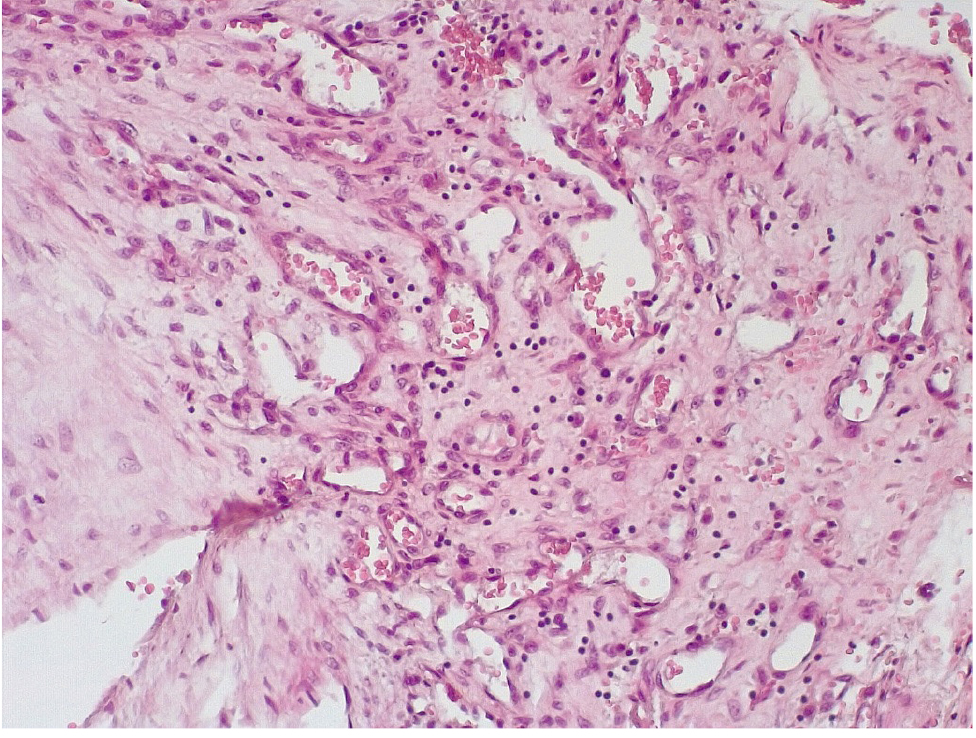

Позднее, спустя 3–7 суток после стентирования КА в просветах имелись пристеночные смешанные фибриново-лейкоцитарные тромбы, которые могли служить источником развития тромбоэмболических осложнений мелких дистальных ветвей коронарного кровотока и развитием острого инфаркта миокарда (рис. 4).

Маркер эндотелиальной дисфункции – фактор Виллебранда (ФВ) ярко экспрессировался в клетках эндотелия КА и субинтимально, что могло свидетельствовать о выраженной дисрегуляции коагуляционных свойств крови (рис. 5). В то же время экспрессия белка CD31 в указанные сроки после стентирования была слабовыраженной, что могло указывать на выраженные дистрофические изменения эндотелиальных клеток КА.

В течение 7–15 суток после стентирования КА наряду с формированием пристеночных фибриновых тромбов с признаками организации в стенках атером наблюдались репаративные процессы, связанные с неоангиогенезом в виде образования мелких тонкостенных кровеносных сосудов капиллярного типа, окруженных мелкими лимфоцитарными, гистиоцитарными клеточными инфильтратами (рис. 6, 7).

Через 3–7 суток и позднее, спустя 7–15 суток после стентирования КА, в просветах КА отмечаются пристеночные смешанные (фибриново-лейкоцитарные), фибриновые тромбы с признаками организации, что сочетается с явлениями неоангиогенеза стенки артерии. Данный патологический процесс ремоделирования стенки КА после стентирования может отражать, с одной стороны, необратимые повреждения клеток эндотелия, ведущие к микротромбообразованию, а с другой – отражать репаративные процессы в исходе воспаления.